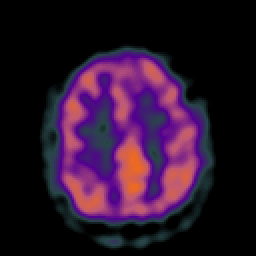

Vascular Malformation (at rest): perfusion SPECT study #1 -- Slice #18

[Home][Help][Clinical] Slice 18